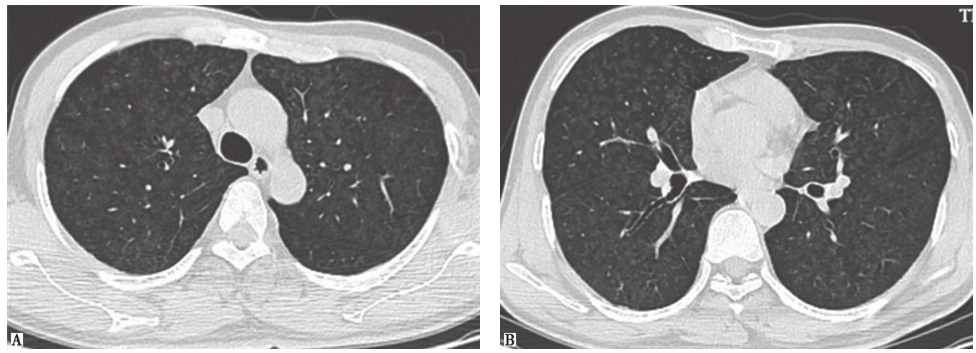

图3肺癌伴肺内转移CT表现

女性患者,45岁,肺癌伴肺内转移。胸部CT见两肺广泛粟粒状小结节影

图4癌性淋巴管炎胸部CT表现

女性患者,55岁,胃癌。胸部CT可见双侧少量胸腔积液伴网格状周边型结节,呈癌性淋巴管炎表现